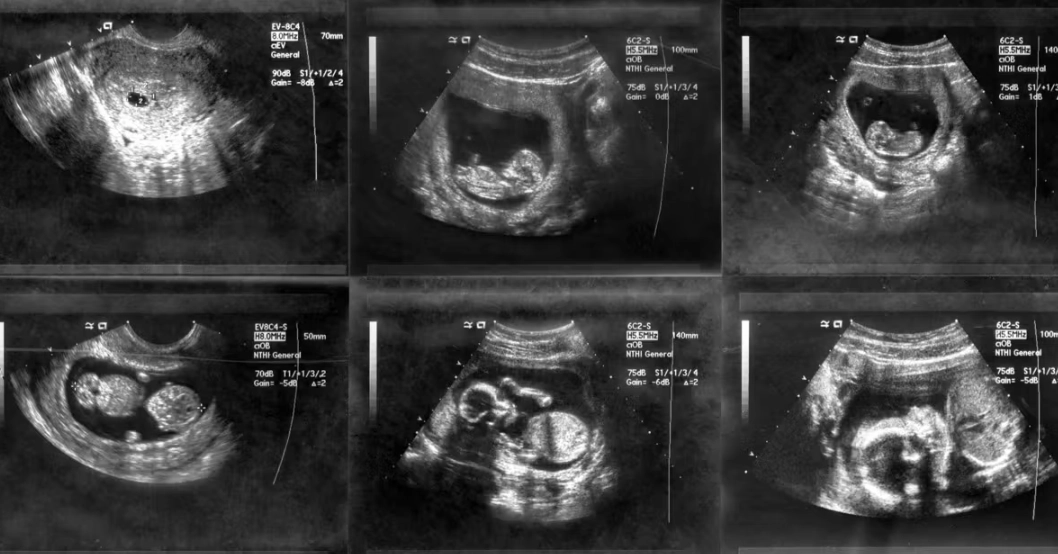

This is the core of it, right? You want to know if you'll see a little bean, a heartbeat, something that makes it feel "real." At one month pregnant (or about 4 weeks gestational age), the embryo is incredibly tiny – we're talking about the size of a poppy seed. It's just beginning to implant and grow.

So, an ultrasound this early is often a transvaginal one (where a probe is inserted into the vagina). It gets a closer, clearer view than an abdominal scan. Here's the breakdown of what a sonographer or doctor is typically looking for at this stage:

Can it detect twins at 1 month?

It's possible, but not reliable. You might see two gestational sacs, but at this stage, it's also possible for one sac to be hidden or for one sac not to develop further (vanishing twin syndrome). Twin confirmation is much more solid around 8 weeks.